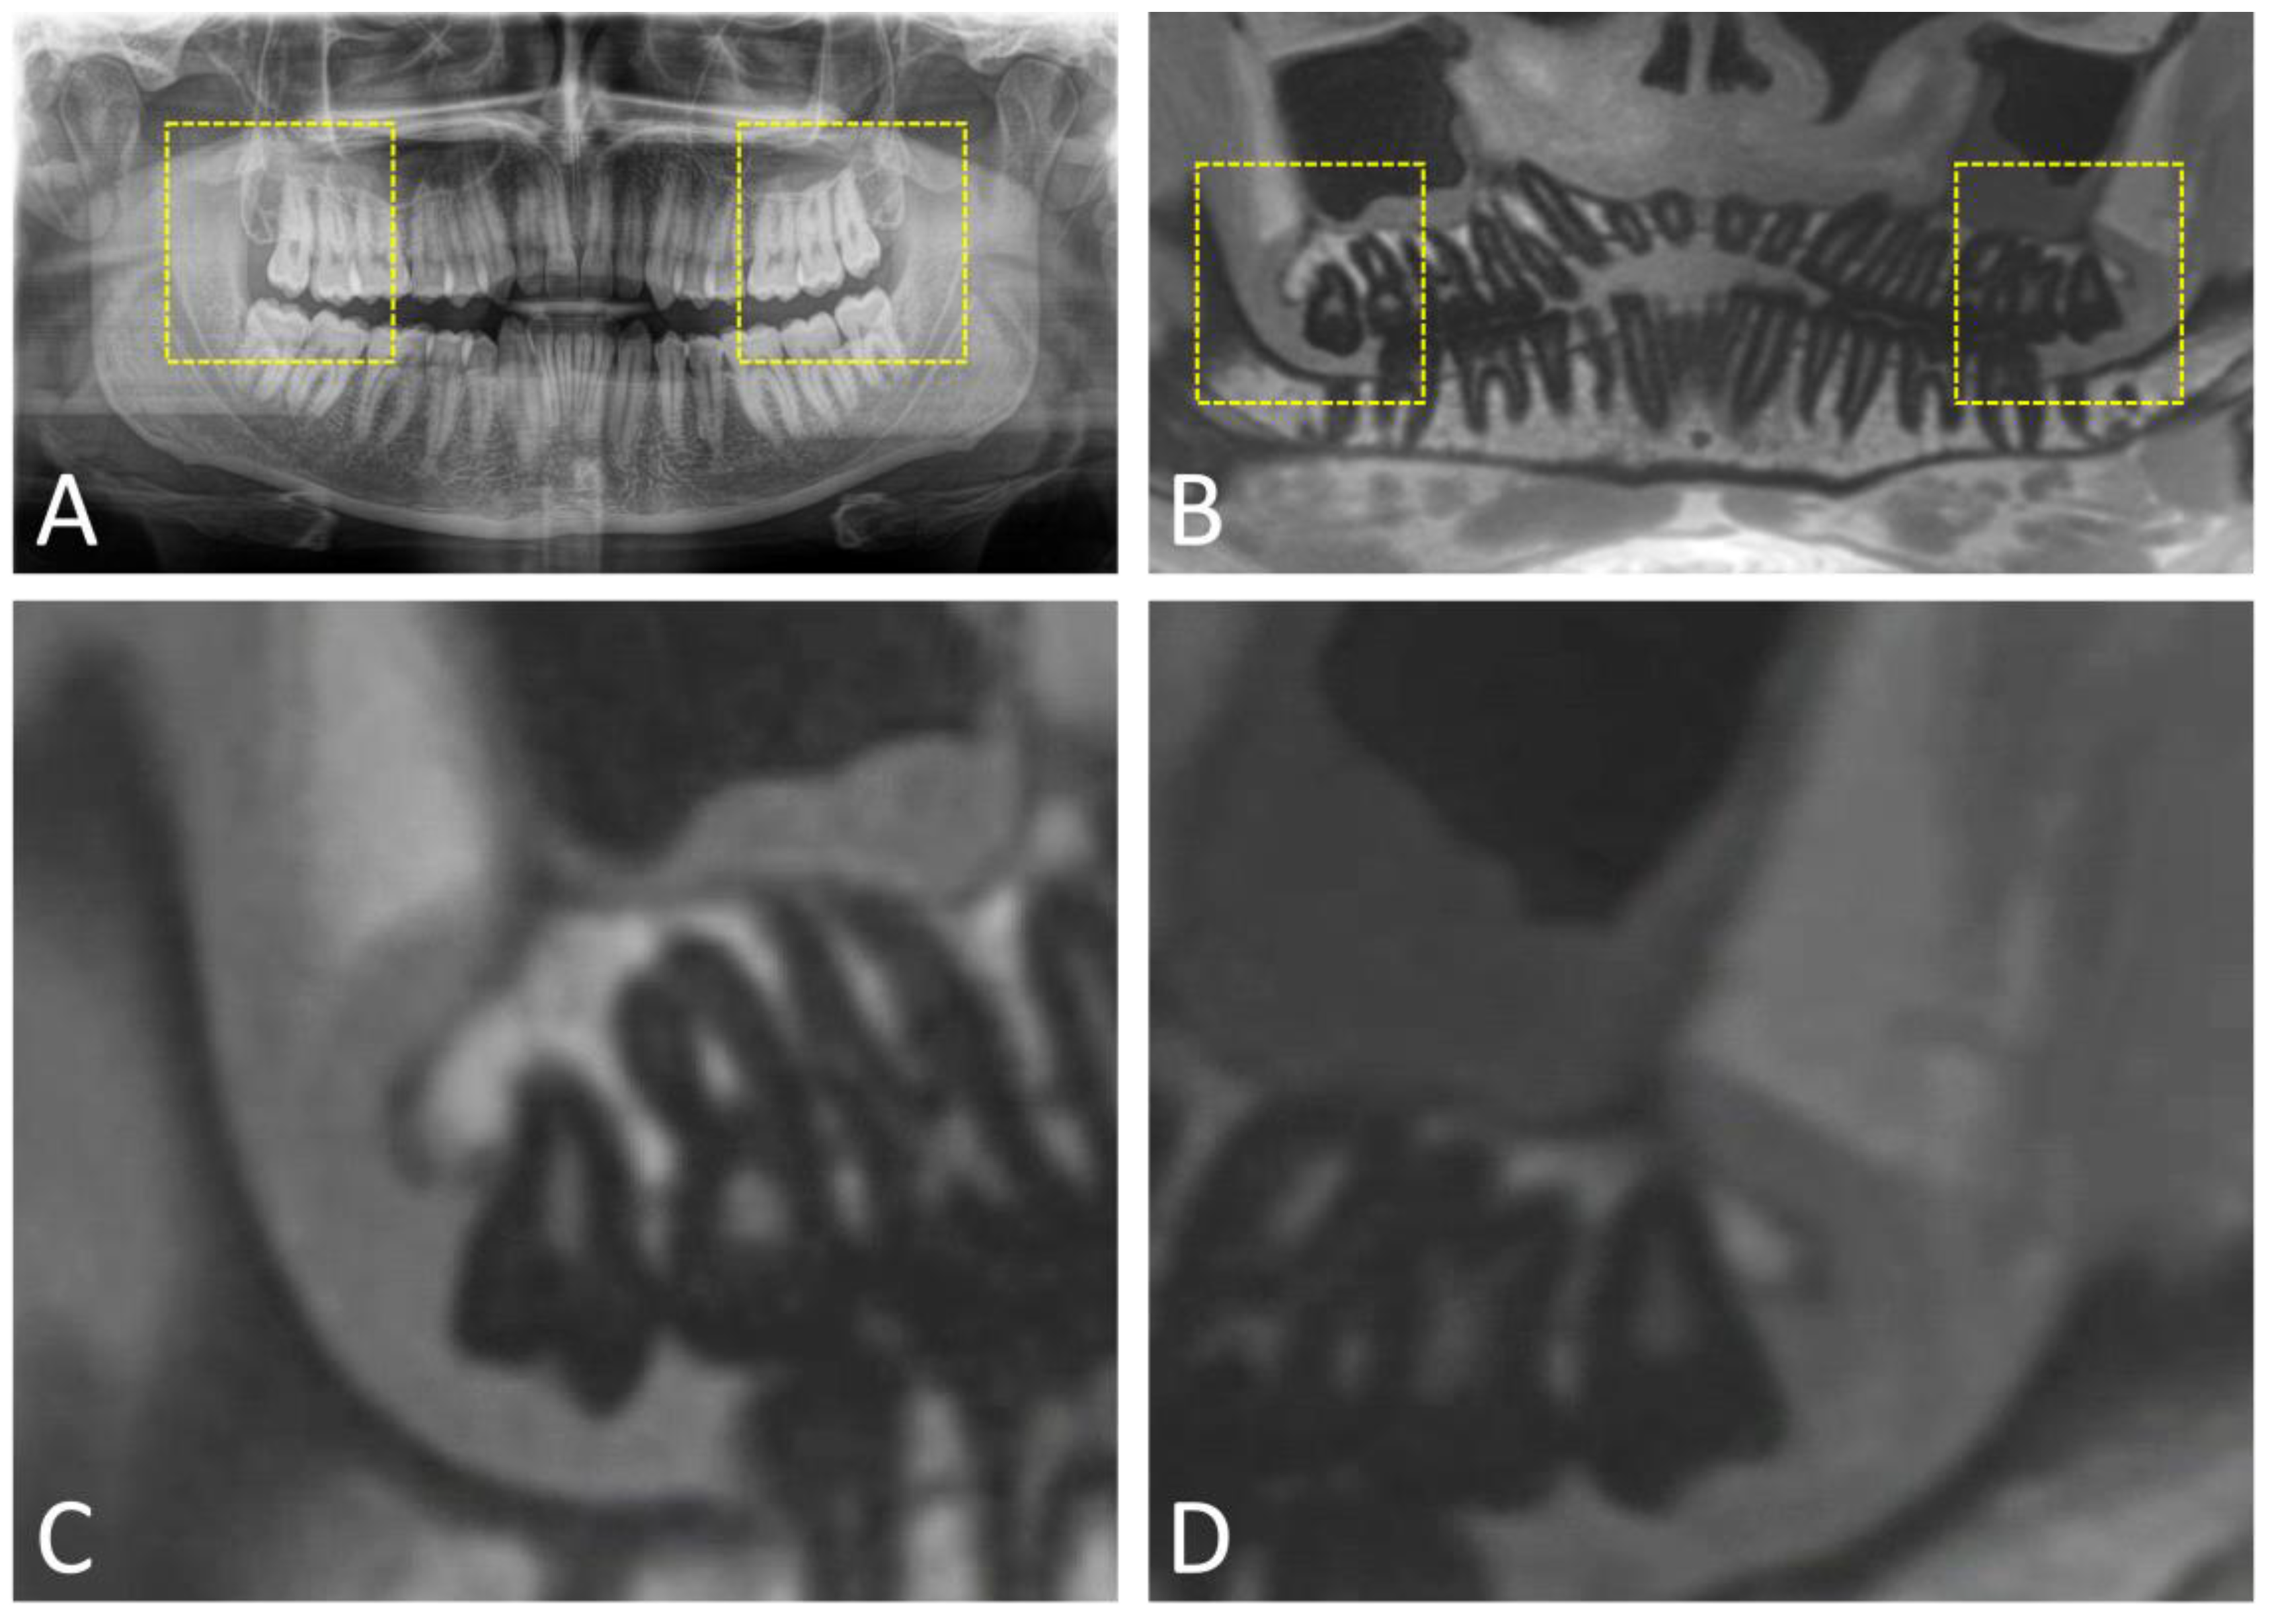

- Al-Haj Husain, A.; Schmidt, V.; Valdec, S.; Stadlinger, B.; Winklhofer, S.; Schönegg, D.; Sommer, S.; Özcan, M.; Al-Haj Husain, N.; Piccirelli, M. MR-orthopantomography in operative dentistry and oral and maxillofacial surgery: A proof of concept study. Sci. Rep. 2023, 13, 6228. [Google Scholar] [CrossRef] [PubMed]